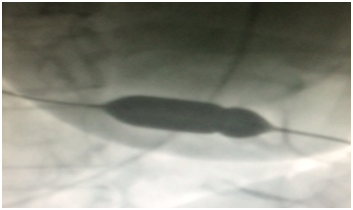

Daxil olarkən xəstənin A/T 120/92mm Hg s., Ps-120 v/dəq, THS-21/dəq. Fizikal müayinədə ağciyərlər üzərində vezikulyar tənəffüs eşidildi, ürək tonları karlaşmışdır. EKQ-də (şəkil 1.) ritm sinus, düzgün, alternans müşahidə edildi. Exokardioqrafik müayinədə parasternal uzun pəncərədə perikard boşluğunda təkrarlanan maye aşkarlandı, miqdarı dəqiq ölçülərək bütün divarlar ətrafında 15-17mm, sağ mədəcik üzərində 13mm qeyd edildi. Təkrarlayan perikardial effuziya səbəbilə xəstəyə ümumi anesteziya fonunda 6.0 x 40mm balon vasitəsilə plevroperikardial pəncərə açıldı.(şəkil 2,3,4,5)